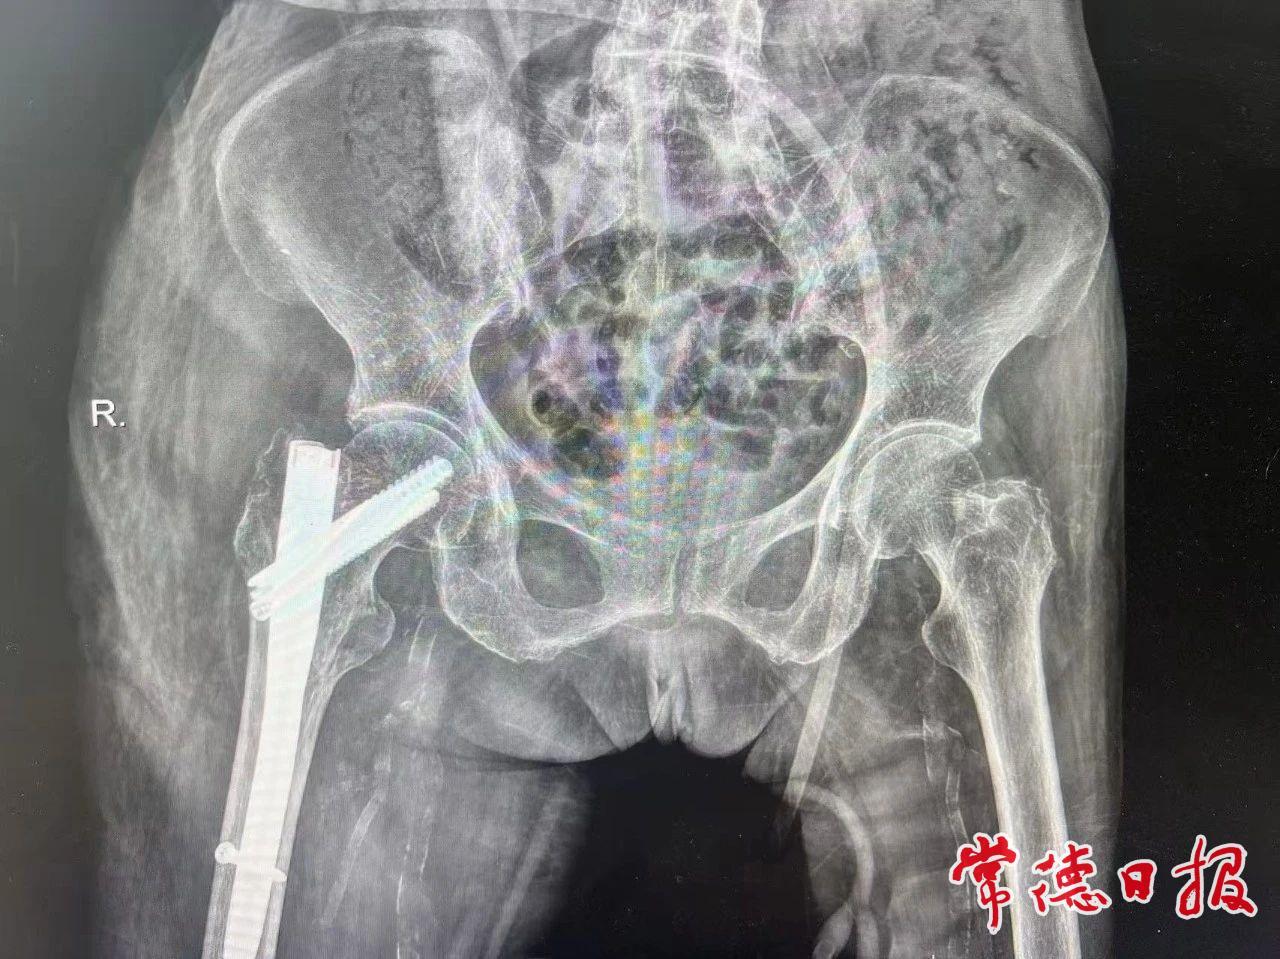

房奶奶患有骨质疏松症,合并糖尿病、心房颤动等基础性疾病,经诊断为右侧股骨转子间骨折。这类骨折被称为“人生最后一次骨折”,如得不到有效治疗,半年内死亡率高达40%。市第一中医医院骨伤二科(创伤二病区)通过术前多学科评估,次日即为患者实施微创InterTAN髓内钉固定术,仅在皮肤切开3个小孔,通过影像引导精准复位骨折并置入髓内钉。术后第一天患者即可完全坐立进食,半个月后康复出院,术后1月左右便能行走活动。